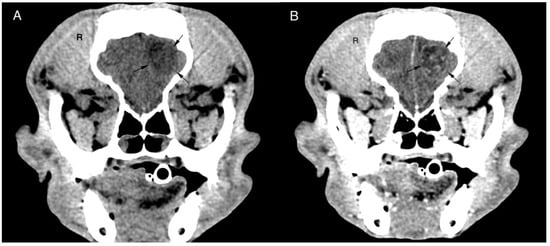

| Boxer | F | N | 9 | 28.5 | Seizures | Lumbosacral pain | Right occipital lobe | 2 | 1st Anaplastic oligodendroglioma grade III 2nd Gliosarcoma grade IV | 1st Temozolomide (76.9 mg/m2 for 5 días every 3 weeks) 2nd Toceranib phosphate (2.8 mg/kg 3 times weekly) | CT & biopsy confirmed | 241 | Euthanasia due to tumour regrowth |

| French Bulldog | F | Y | 8 | 8.9 | Seizures | Decrease pupillary reflex OD | Right olfactory lobe | 2 | 1st Anaplastic oligodendroglioma grade III 2nd Anaplastic oligodendroglioma grade III | Temozolomide (93.0 mg/m2 for 5 days every 3 weeks) | CT & biopsy confirmed | 428 | Euthanasia due to aspiration pneumonia two days after the second surgery. CT ruled out IC haemorrhage |